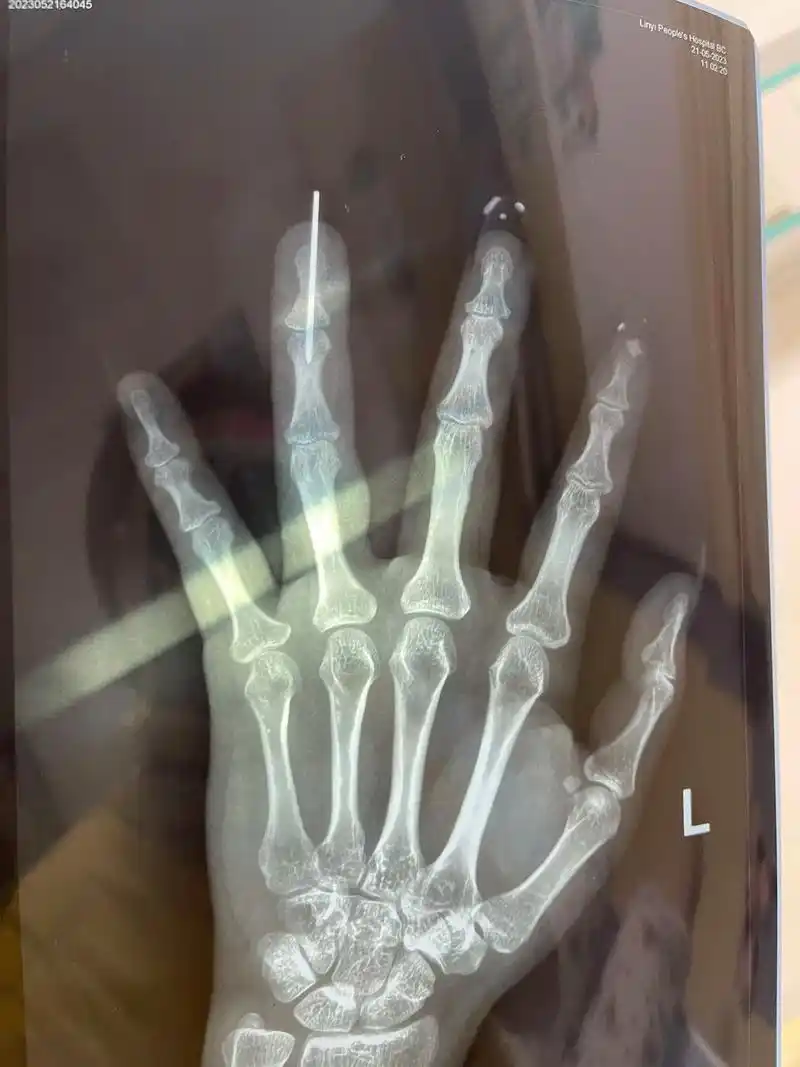

经过dr检查后,孙主任发现患者环指完全离断,中指尺侧指固有动脉及神经